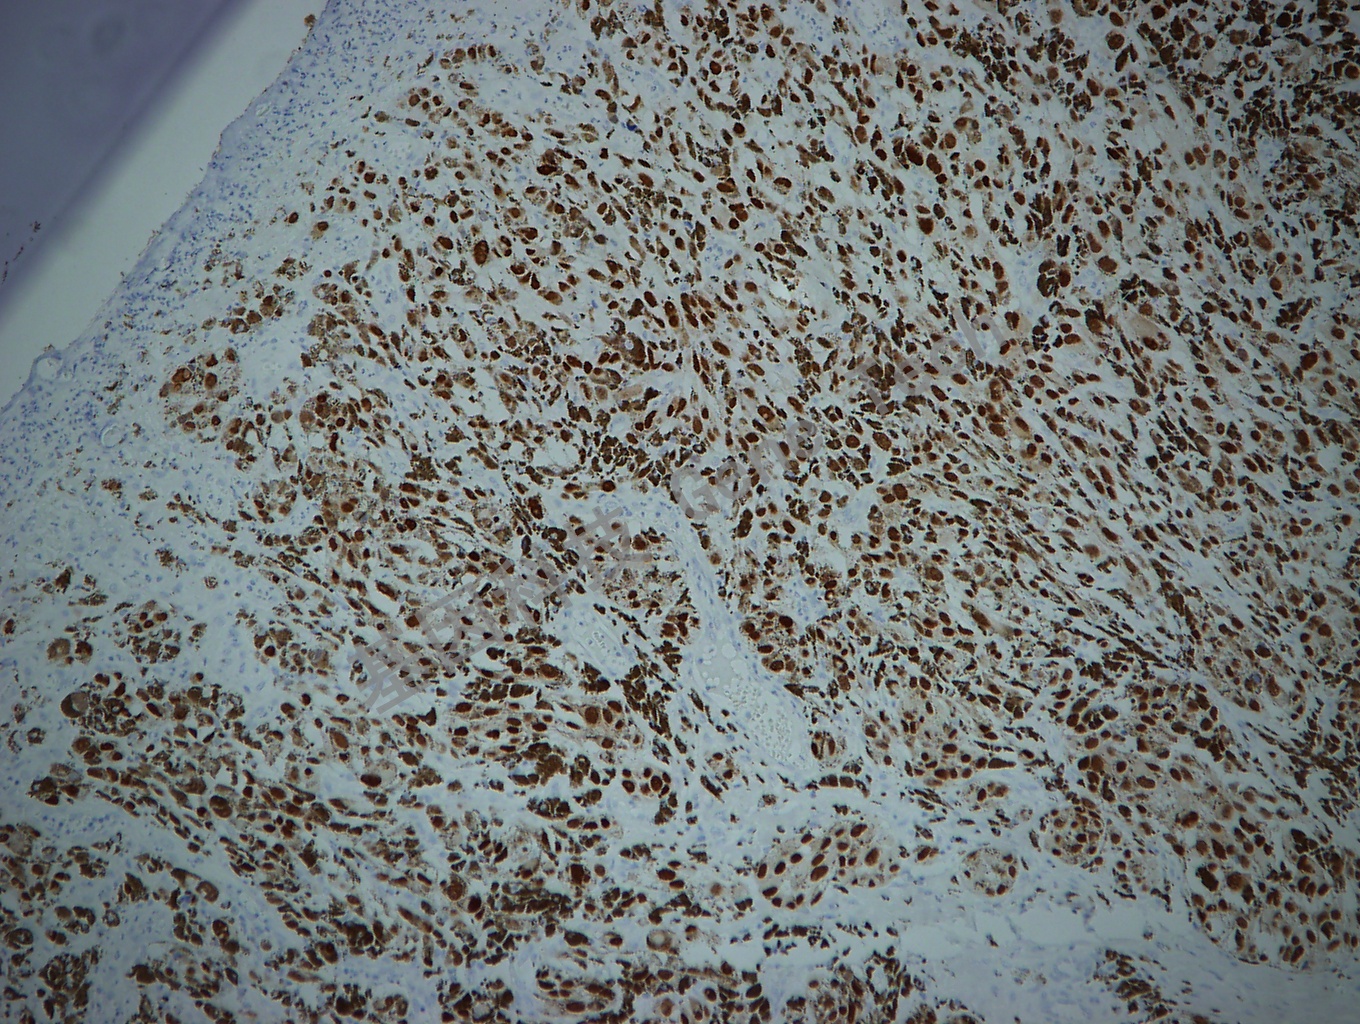

神经鞘瘤石蜡切片,用 SOX-10(GT2210)染色,细胞核阳性,DAB 显色。